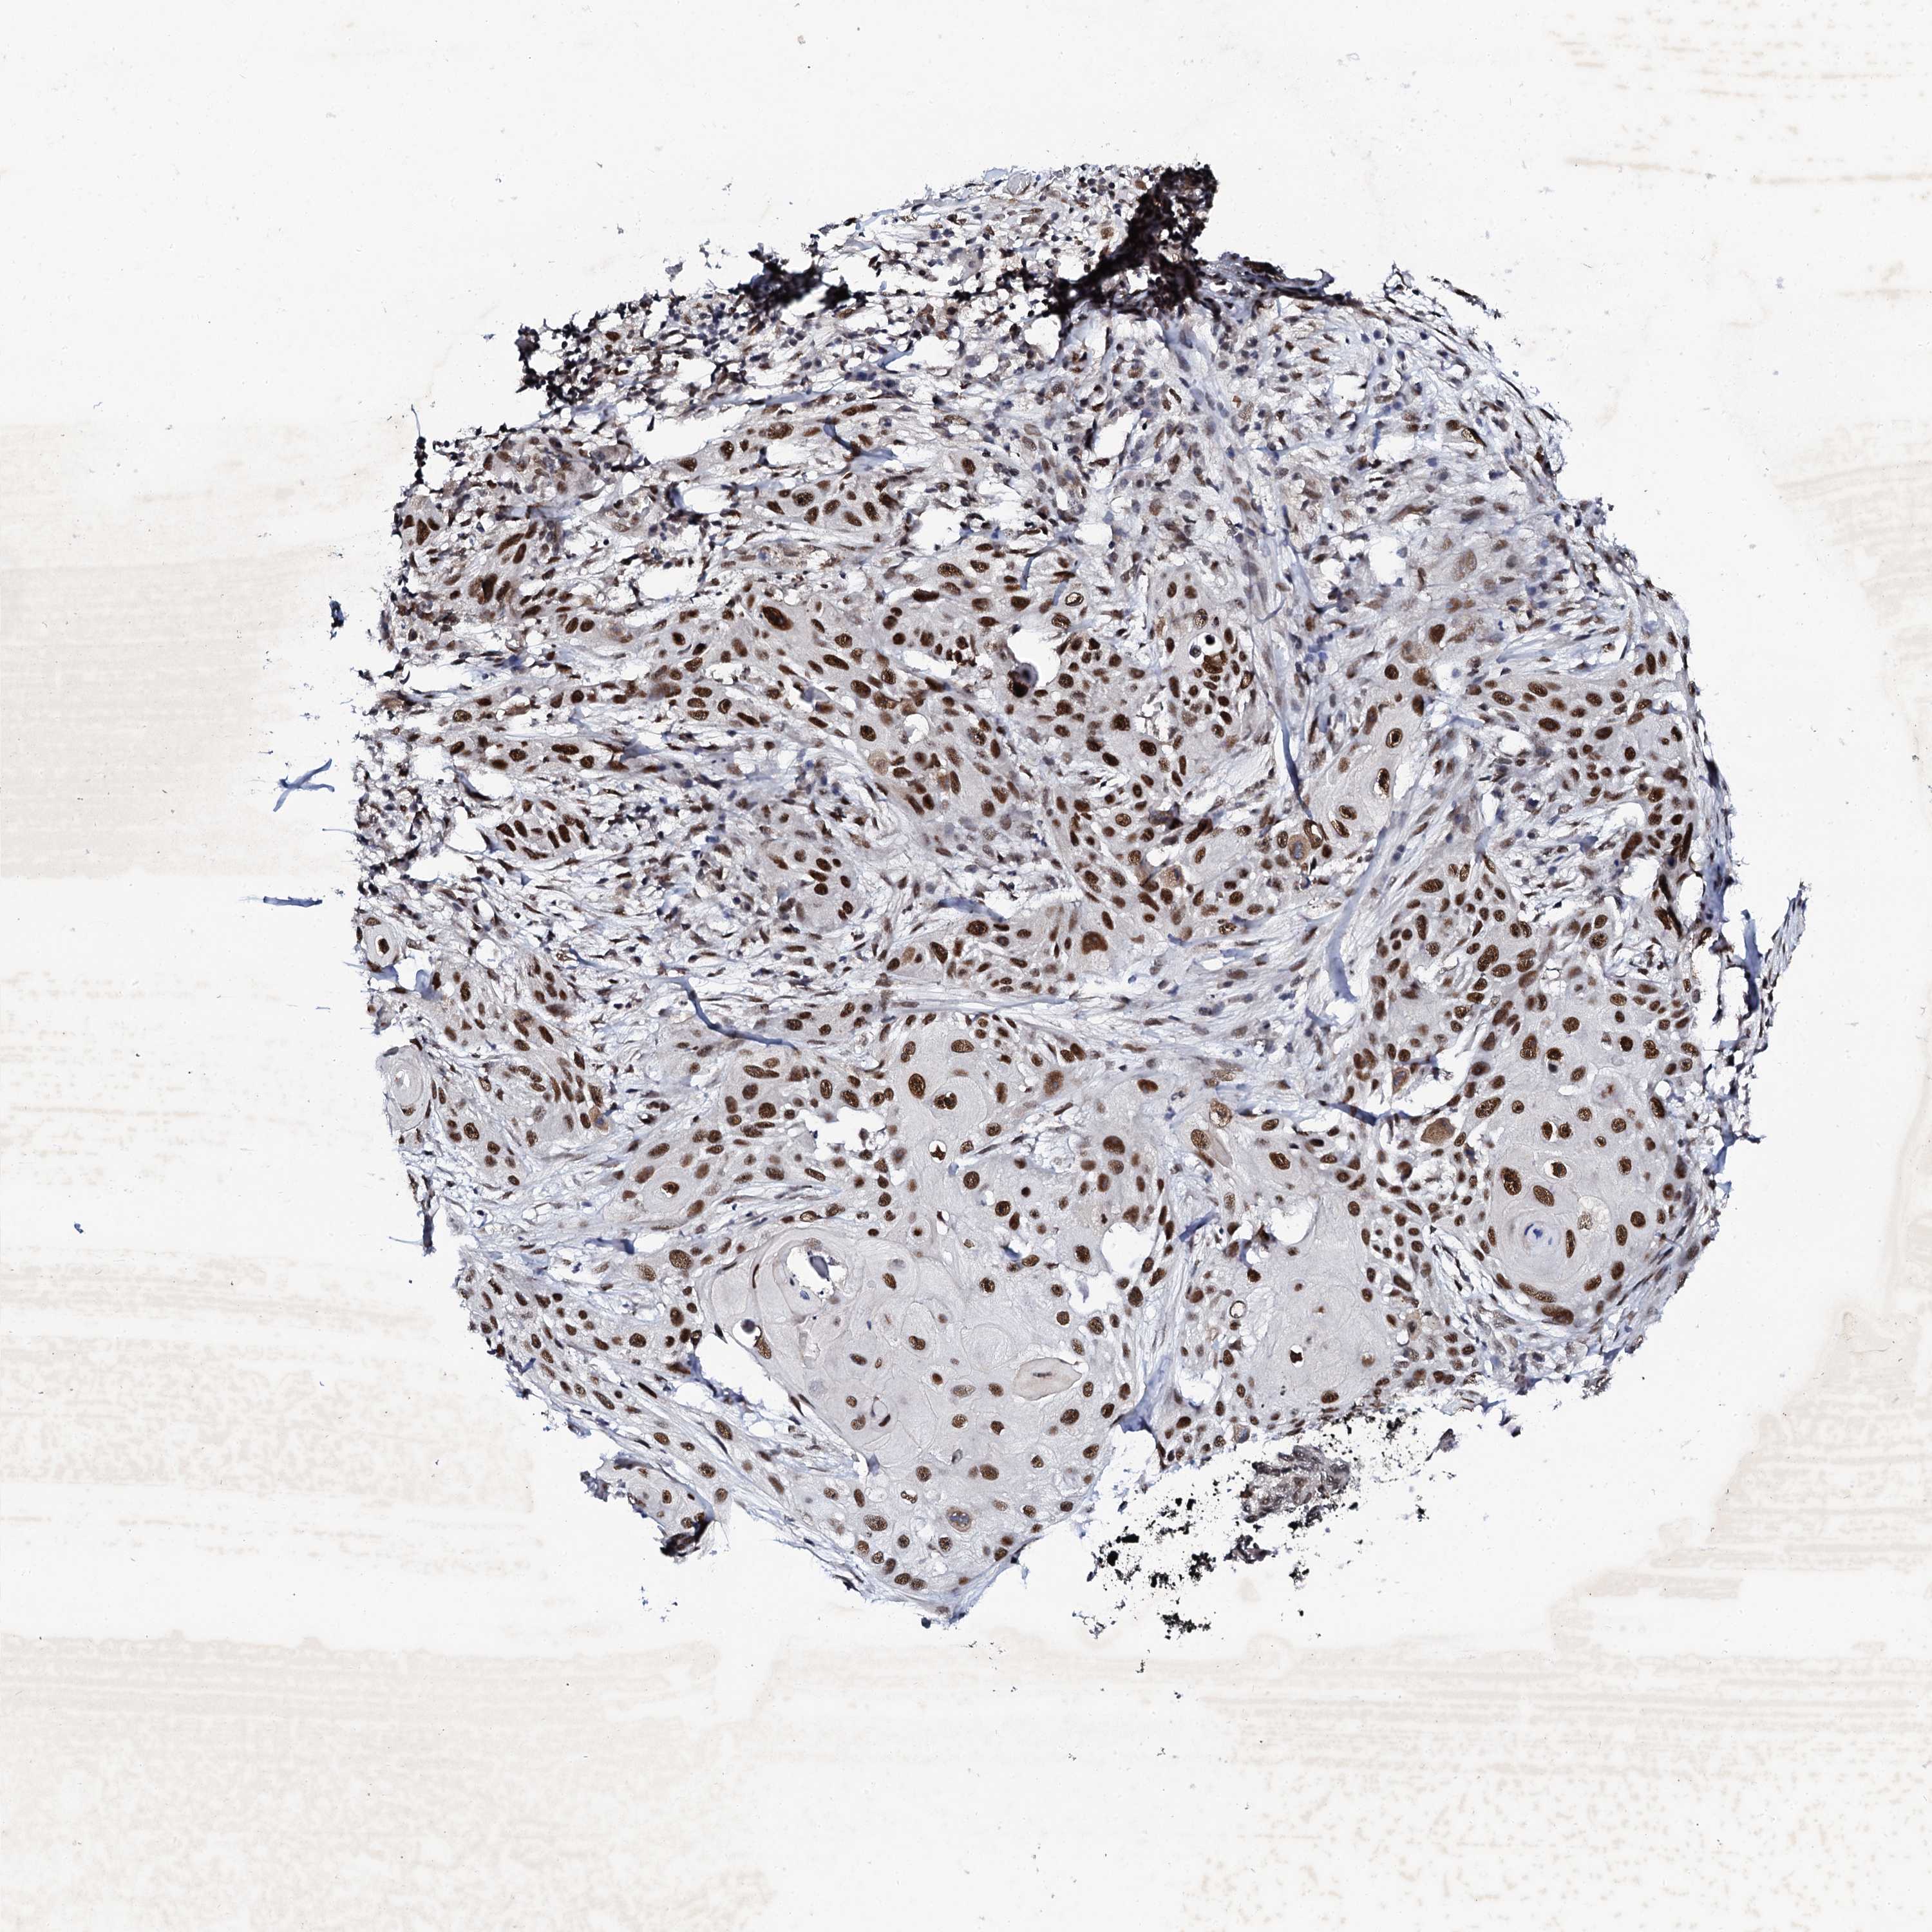

SKIN CANCER - Protein expressioni

A mouse-over function shows sample information and annotation data. Click on an image to view it in a full screen mode. Samples can be filtered based on level of antibody staining by selecting one or several of the following categories: high, medium, low and not detected. The assay and annotation is described here.

Antibody staining in the annotated cell types in the current human tissue is reported as not detected, low, medium, or high, based on conventional immunohistochemistry profiling in selected tissues. This score is based on the combination of the staining intensity and fraction of stained cells.

Each image is clickable and will lead to virtual microscopy that enables deeper exploration of all samples and also displays staining intensity scores, fraction scores and subcellular localization as well as patient and tissue information for each sample.

Antibody HPA040168

Squamous cell carcinoma, metastatic, NOS

Squamous cell carcinoma, NOS